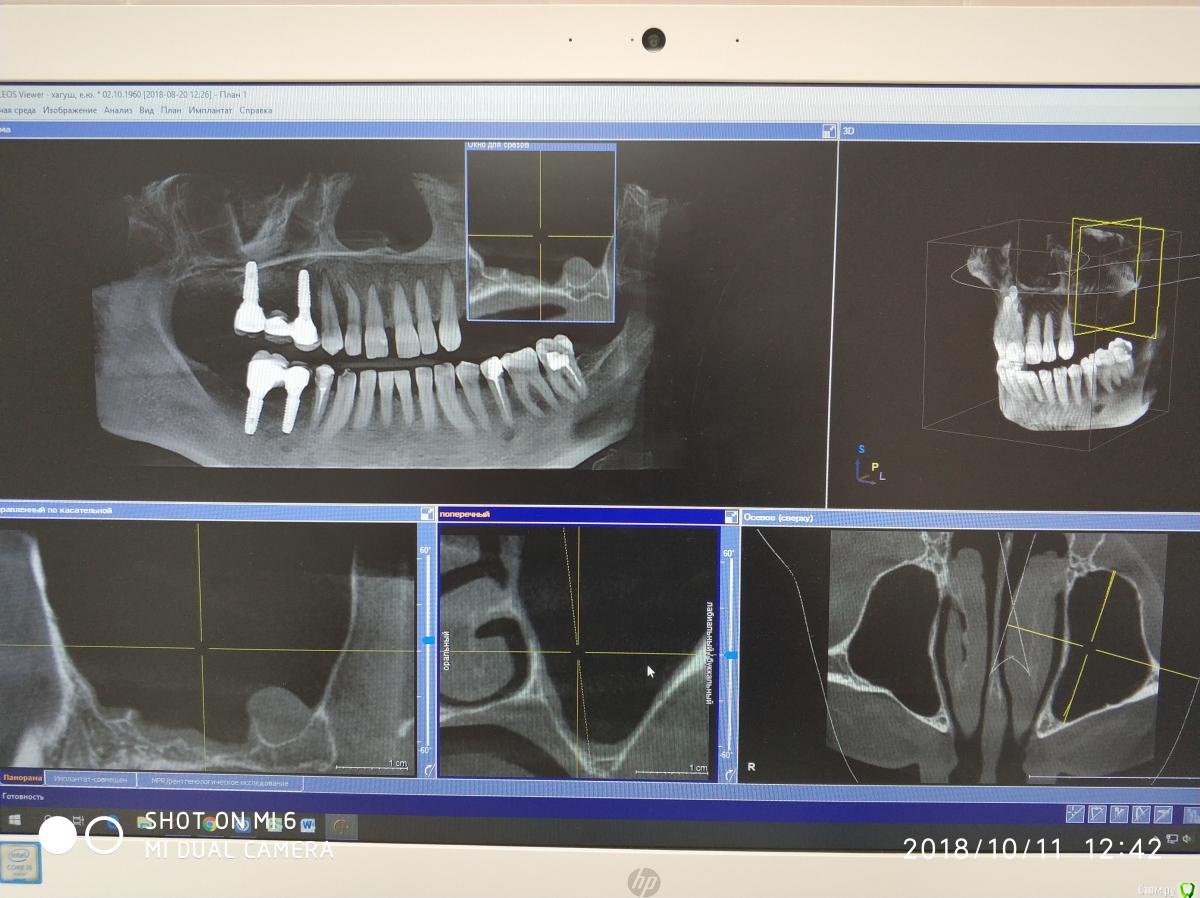

Nazim_NV86 Опубликовано 11 октября, 2018 Автор Поделиться Опубликовано 11 октября, 2018 Появилась свежая КЛКТ Ссылка на комментарий

Nazim_NV86 Опубликовано 11 октября, 2018 Автор Поделиться Опубликовано 11 октября, 2018 (изменено) Женщина. Примерно 50-53. Скрины синуса сделал, но замотался и забыл выложить. Синусы вч оба чистые. Слева правда есть маленькое мукоцеле. Сегодня предложил ей снять коронки и походить с формирователями. По семейным причинам уехала к дочери помогать. Отложили на месяц. Так у нас есть месяц на расследование ) Изменено 11 октября, 2018 пользователем Nazim_NV86 Ссылка на комментарий

Nazim_NV86 Опубликовано 12 октября, 2018 Автор Поделиться Опубликовано 12 октября, 2018 Срезы пазух. На чувствительность языка жалоб не слышал. Как приедет тесты сделаю. Ссылка на комментарий